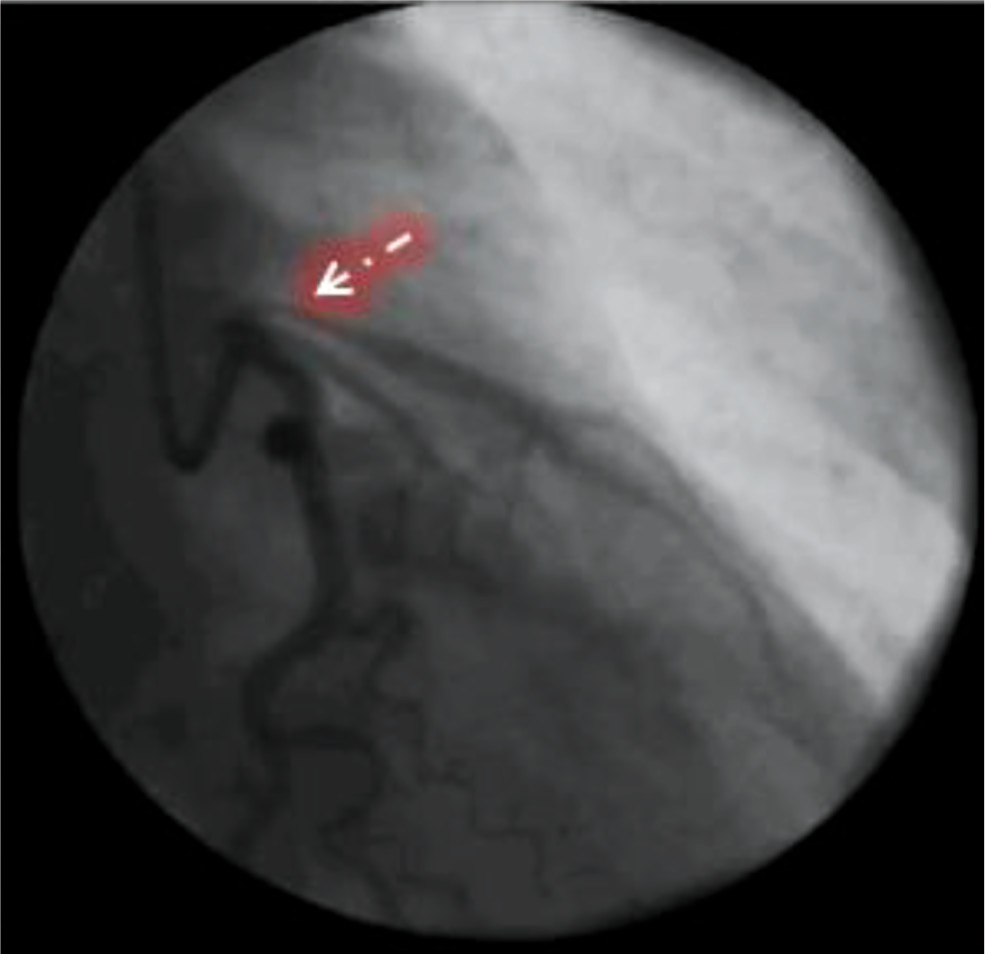

Спустя 8 нед от момента развития ИМ в плановом порядке пациентке были проведены контрольная КАГ и ОКТ КА. В случае СДКА ОКТ также необходима для оценки прилегания стента к КА, так как после разрешения интрамуральной гематомы просвет сосуда увеличивается и может не соответствовать размеру ранее имплантированного стента [5]. По результатам повторной КАГ: ПМЖА, ОВ — без гемодинамически значимых изменений, стенты проходимы.

При выполнении ОКТ ПМЖА обнаружены недостаточное прилегание страт в проксимальной и средней части стента и отсутствие его эндотелизации, а также разрыв интимы в приустьевом отделе ПМЖА и протяжённая (>20 мм) субинтимальная гематома, выходящая за пределы области стентирования до бифуркации ПМЖА с ДВ. На всём протяжении ПМЖА визуализировалась трёхслойная структура её стенки без признаков атеросклеротического поражения (рис. 6, 7).

Рис. 6. Изображение оптической когерентной томографии передней межжелудочковой артерии в приустьевом отделе. Стрелкой указаны разрыв интимы с формированием субинтимальной гематомы, а также мальпозиция страт стента.

Fig. 6. Optical coherence tomography image of AIVA in the aortic section. The arrow indicates intimal rupture with formation of subintimal hematoma, as well as malposition of the stent strut.

Рис. 7. Визуализация при оптической когерентной томографии субинтимальной гематомы на уровне средней трети передней межжелудочковой артерии.

Fig. 7. OCT visualization of subintimal hematoma at the level of the middle third of AIVA.

По данным ОКТ ОВ, прилегание стента хорошее на всём протяжении, мальппозиции нет, признаки атеросклероза отсутствуют. Одномоментно проведена баллонная ангиопластика в проксимальном отделе стента ПМЖВ баллоном TREK 3,25×25 мм под давлением 12 атм. При повторной ОКТ ПМЖА отмечено улучшение прилегания страт стента, значимой мальппозиции нет.

Таким образом, полученные результаты ОКТ с высокой долей вероятности свидетельствуют о том, что причиной ИМБОКА у нашей пациентки стала СДКА 3-го типа.